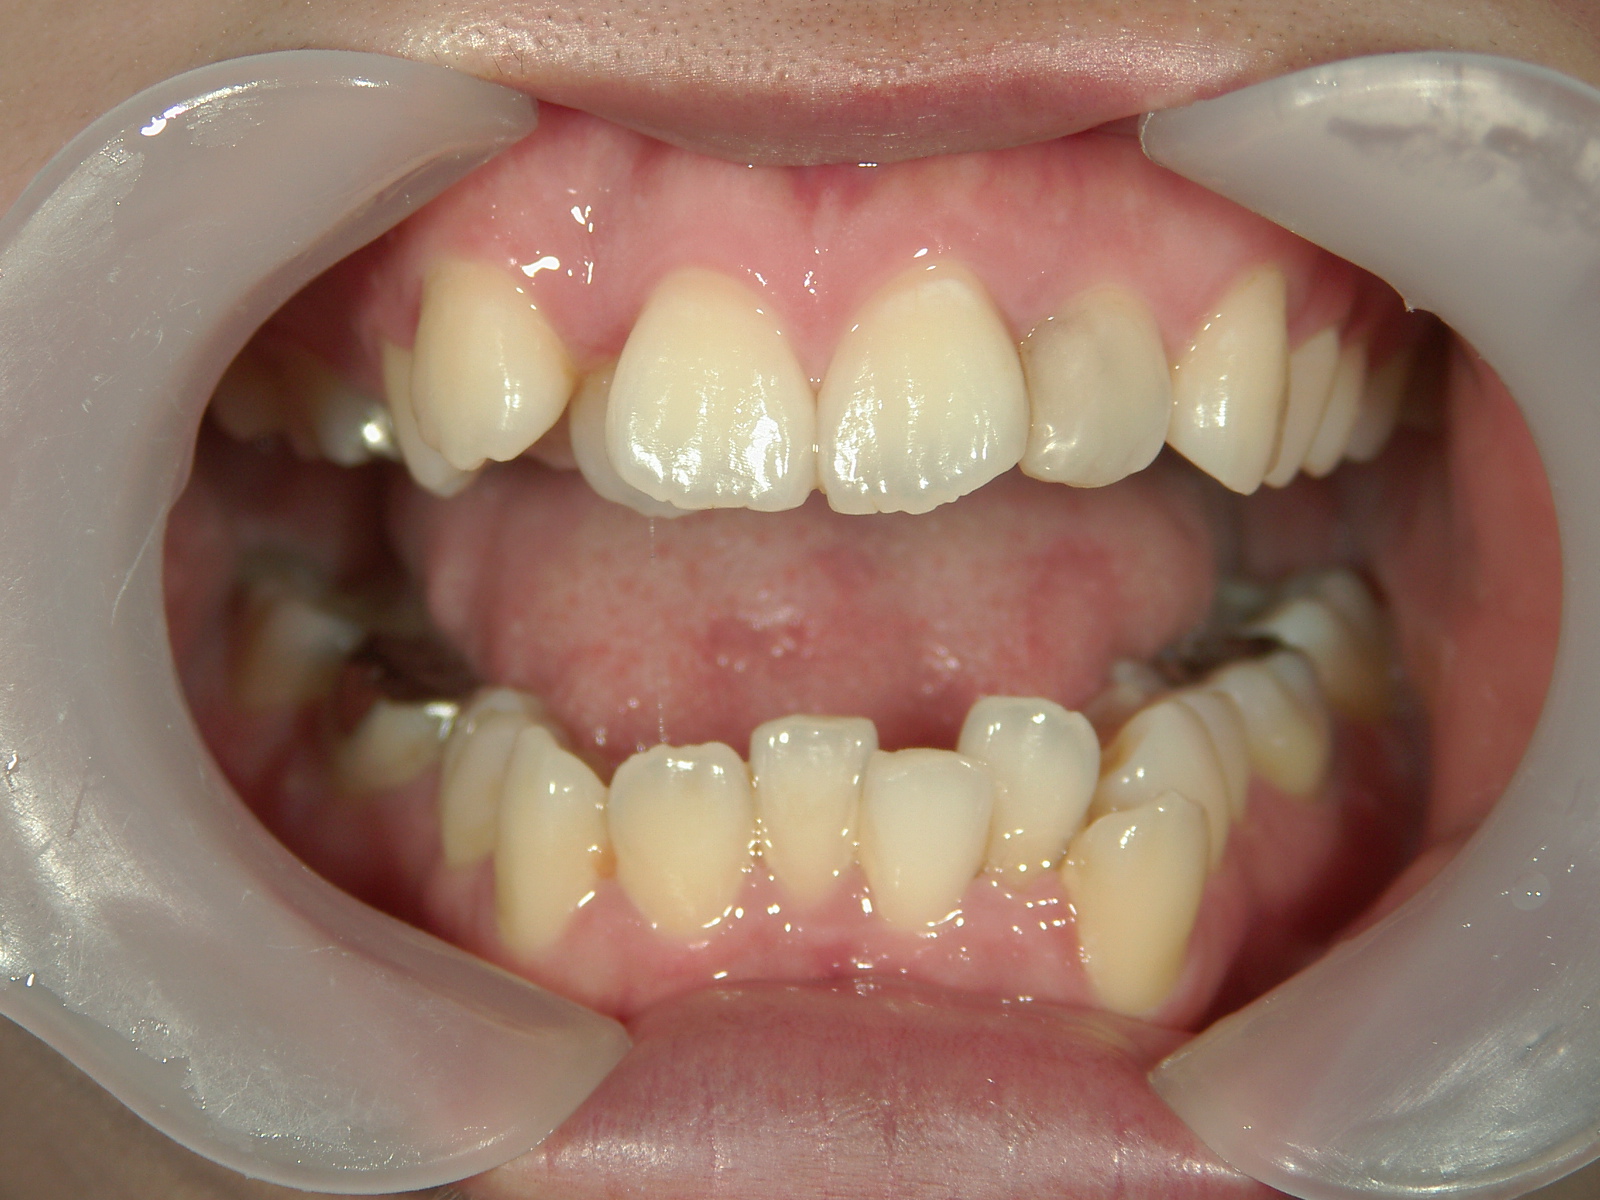

舌側ワイヤー矯正 症例(25)

主訴: 歯並びが気になる

カテゴリー : ガタガタ(叢生)